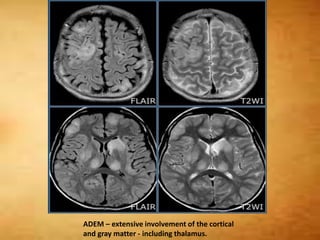

ADEM – extensive involvement of the cortical

and gray matter - including thalamus.

MS vs ADEM •ADEM typically following arecent (1-2 weeks prior) viral infection or vaccination. • Slight male predominance • Symptoms are more systemic • Involvement of the callososeptal interface is unusual . basal ganglia is often involved . • MTR and diffusivity may help distinguish ADEM from multiple sclerosis. In multiple sclerosis both measurements are significantly decreased.

ADEM – extensiveinvolvement of the cortical and gray matter - including thalamus.